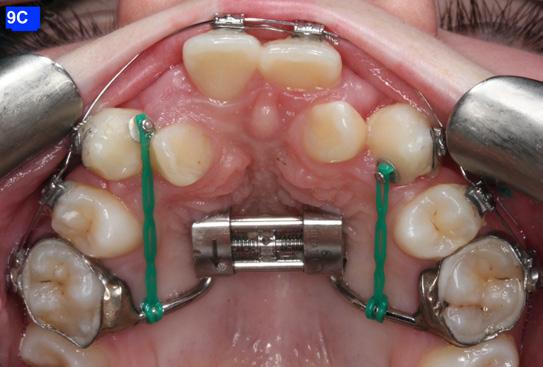

Finally, after 21 months of treatment, the patient and the parents consented to the odontectomy of the maxillary first bicuspids. The informed consent forms for the extractions and placement of TADs were signed by the parent, and all questions were answered. Risks, benefits, alternatives, and the result of no treatment at all were reviewed. Immediately after the odontectomy of #14(5) and #24(12), 1.6 x 8.0 mm AnchorPro (OrthoOrganizers) TADs were placed just mesially to the maxillary second bicuspids.6 In office power arms (a .018 x.025 SS) were fabricated and bonded to the buccal surface of the maxillary cuspids, just above the bracket.7 The purpose of the power arm is to place the applied force as close to the center of resistance of the tooth as possible. In this manner the line of action (power hook to the TAD) is parallel to the occlusal plane. The source of the force is an EC, and it must be replaced at least bi-weekly. Both arches had a .018 SS arch wire. There was a small off-center bend (tip-back, gable bend) “V” pointing occlusally, mesial to the maxillary second bicuspids.8 The purpose of this bend is to keep the roots parallel during the translation of the cuspids. There was a small OCS between #21(9) and #23(11) to shift the maxillary midline to the right. Another OCS was placed between #32(23) and #34(21) to facilitate the alignment of the mandibular left cuspid (Figure 8-A, B, C, D).

To prevent a disto-lingual moment (rotation) of the maxillary cuspids we attached PC from the lingual button on the cuspids to the framework on the hyrax. The anterior portion of the Hyrax was cut off and the remaining portion served as a TP arch for posterior anchorage. At this point, we were 25 months into treatment (Figure 9-A, B, C, D). The hyrax was removed after 30 months of treatment.

Figure 8A: TADs in situ, frontal view 8B: TAD in situ, right lateral view 8C: TAD in situ, left lateral view 8D: Power arms Figure 9A: Maxilla, occlusal view 9B: Maxilla, occlusal view 9C: Maxilla, occlusal view Figure 9D: After the removal of the Hyrax, occlusal view Figure 10A: Center bend “V” pointing gingivally Figure 10B: OCS between the cuspids and the central incisors Figure 10C: Composite build-ups on the mandibular first molars Figure 10D: Adrian “U” bend spring